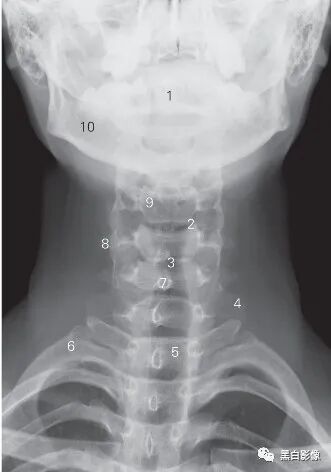

图6-1 颈椎正位DR平片

1 齿状突 odontoid 2 钩椎关节 uncovertebral joint

3 第5/6颈椎间隙 5th/6th cervical intervertebral space

4 第7颈椎横突 7th cervical transverse process

5 第1胸椎椎体 1st thoracic vertebral body 6 第1肋骨 1st rib

7 棘突 spinous process

8 第5颈椎横突 5th cervical transverse process

9 第4颈椎椎体 4th cervical vertebral body 10 下颌骨 lower jawbone